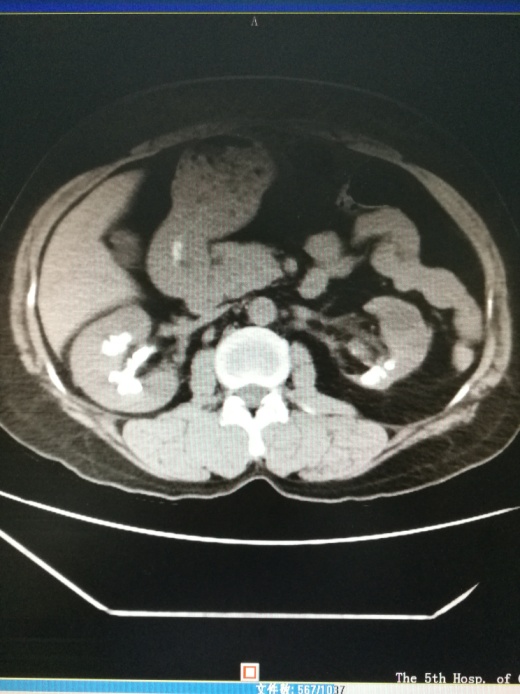

CTU尿路造影

患者右侧肾结石分支肾盏多,肾盏狭长,这样的结石因为外形轮廓酷似‘鹿角’状,被称为“鹿角形肾结石”。同时她的左肾轻度萎缩,是典型的功能性孤立肾合并鹿角形肾结石。”结合入院的进一步完善检查和患者资料,李逊教授认为林阿姨此次手术难度大(取净结石难度大),手术风险高(手术出血风险高)。

肾盏分支多且肾盏狭长